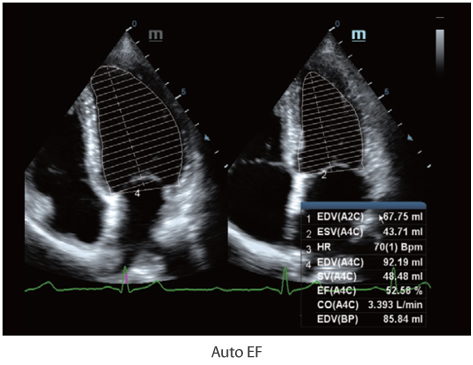

X-Insight to rozwi?zanie umo?liwiaj?ce wnikliw? analiz?, zapewniaj?c bardziej szczeg├│?owy obraz.

Opieraj?c si? na analizie potrzeb klienta, DC-60 Exp X-Insight zosta? zaprojektowany tak, aby znacznie usprawni? diagnostyk?, kt├│ra jest wspomagana przez technologi? eXpress Clarity, eXceptional Intelligence i eXceeding Experience.

Obrazy kliniczne